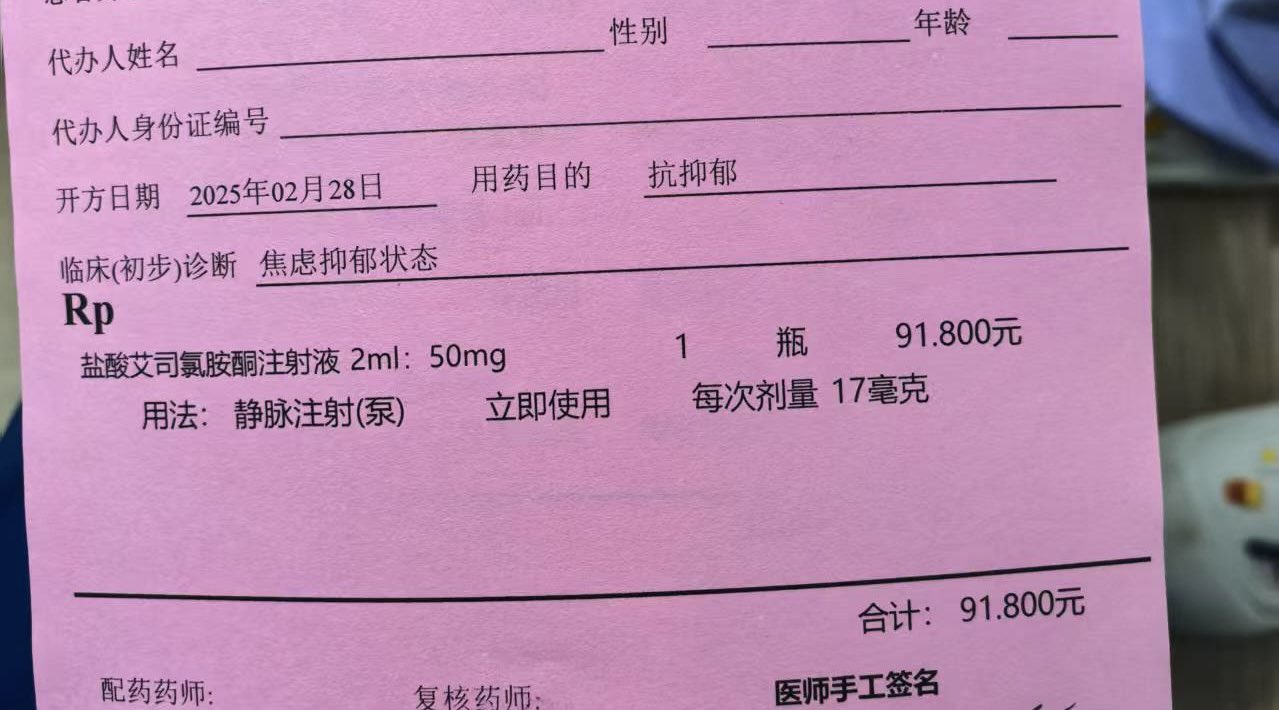

真的会推荐发作的时候或难治性抑郁做氯胺酮🥺关于价格,不算私立医院或住院的情况,一般一次是800...其实以前药费也有吃到过很高

不会像mect那样副作用很可怕,我的感觉是几乎没有负面影响

顺着这个思路用的auv对我效果也很好。那么漫长的寻找和尝试总算有了相对稳定的解法..太好了